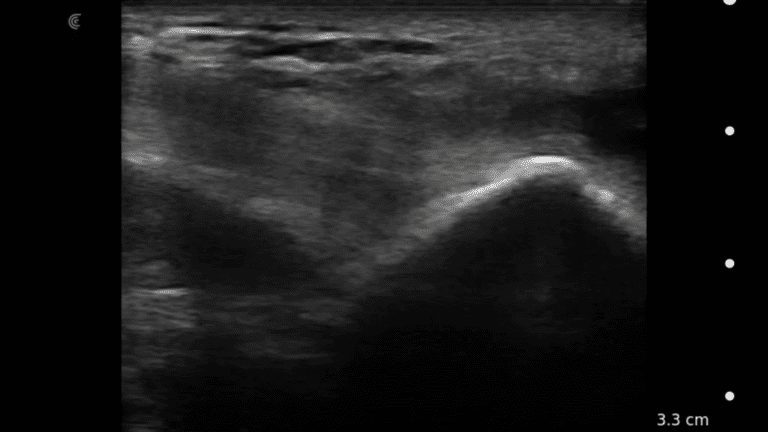

A survey scan of the elbow can identify some of the most common pathologies that cause acute and chronic elbow pain such as tendinosis of the common flexor or extensor tendons, joint effusion, or olecranon bursitis.